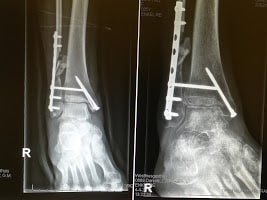

Op maandag 4 april had ik de controle afspraak met de chirurg. Hij was tevreden over de röntgenfoto’s die opnieuw gemaakt waren en tevreden over het functioneren van mijn enkel. De opdracht is nu om in de daarop volgende 6 weken de belasting op te voeren naar 100% belasting op mijn aangedane enkel. Dit betekent dat ik eerst met 1 kruk ga lopen en daarna zonder enig hulpmiddel. Spannend!

Ik vertelde in mijn vorige stukje toch over ‘use it, or lose it’? En dat botweefsel ook levend weefsel is wat zich continu aanpast aan de belasting van het dagelijks leven. Net zoals spierweefsel. Als je spieren traint, word je krachtiger en handiger. Doe je niets, dan neemt de kracht en conditie van je spieren af. Een periode van onderbelasting geeft te weinig stimulus aan de botten om sterk te blijven. Het leidt tot een vermindering van het skeletgewicht. Er treedt calciumverlies op. Dit noemt men osteopenie. En dan kijken we nu even naar mijn röntgenfoto’s… De linker foto is vlak na mijn operatie (8 januari) gemaakt. En de rechter foto op 4 april. Als u goed kijkt naar de botten van mijn voet, en ook mijn scheenbeen (grote verticale bot), dan is te zien dat ze minder wit zijn… Zo ziet u maar hoe belangrijk beweging is voor ons lichaam!!! In mijn geval zullen mijn botten zich weer gaan aanpassen naarmate ik weer meer zal gaan staan, lopen en sporten. Gelukkig!